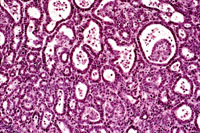

Higher magnification of liver lesions in a 4-week old AL-TAg x AL-myc mouse.

Higher magnification of a well differentiated cholangiocarcinoma in a 4-week old AL-TAg x AL-myc mouse.